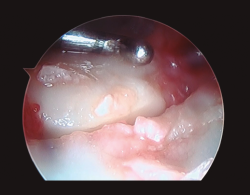

- Artroscopia de muñeca con sistema de tracción longitudinal a 10 N y vías artroscópicas estándar 3-4 y 6R para evaluar la articulación radiocarpiana y las vías mediocarpiana ulnar (MCU) y radial (MCR) en el caso de la articulación mediocarpiana, utilizando para ello una óptica de 2,3 mm y 30°(2,17), mediante técnica de artroscopia en seco(23)(Figura 2). En este tiempo quirúrgico artroscópico se evaluó: la presencia de escalón articular, la rotación de los fragmentos articulares y la existencia de lesiones asociadas al nivel del complejo del fibrocartílago articular (CFCT), así como al nivel de los ligamentos extrínsecos e intrínsecos de la muñeca(17)(Figura 3). En primer lugar, se evalúo la articulación radiocarpiana y, a continuación, la articulación mediocarpiana.

Figura 3. Desde el portal de visión radiocarpiano 3-4 observamos un importante escalón articular en la superficie de la extremidad distal del radio. Al fondo de la imagen se aprecian los ligamentos radiocarpianos volares, con integridad de los mismos.